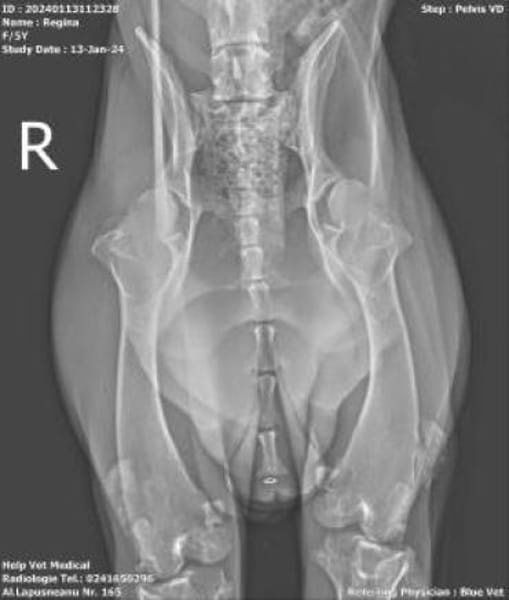

Nach der ersten Stabilisierung durch hochwertiges Futter und Vitamine zeigte sich aufgrund ihres Gangbildes schnell, dass mehr dahintersteckt: Röntgenuntersuchungen ergaben eine Hüftgelenksdysplasie (HD) sowie eine beidseitige Patella-Luxation. Ob diese Einschränkungen genetisch bedingt sind oder durch schlechte Haltung und Aufzucht entstanden, lässt sich nicht sicher sagen.

Die Röntgenaufnahmen zeigten wir natürlich deutschen Spezialisten die uns von jeglichen Operationen abgeraten haben. Es wäre eher eine Qual für Regina wie das es ihr nützt.